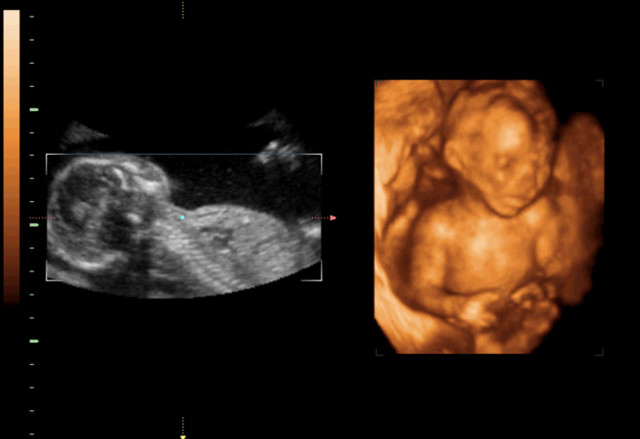

30岁的小孙就有唇裂,修补过的疤痕仍很分明。在最近一次三维B超显示,腹中的胎儿居然中度唇裂。她通知大夫,由于她诞生就有唇裂,小时老是被讪笑和厌弃。所有,无论怎样也要流掉腹中的宝宝,她不想让她的孩子再经历这样的经历。

大夫却通知小孙,现在已经孕21周,如果引产对身材损伤十分大,如果在次怀孕,不能包证就不会得唇腭裂,第二次仍会怀上唇腭裂宝宝的几率约为4%,假如怀过两次唇腭裂的宝宝,第三次怀上唇腭裂宝宝的几率会提升到14%。如今婴儿唇腭裂整形手艺,已经十分告捷,即使是重度的唇腭裂,仍是能够修补得简直看不出来了。倡议把孩子生上去,不要由于这点瑕疵,就将宝宝的性命闭幕。